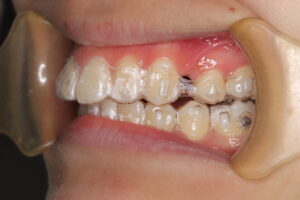

患者さんは、上の前歯がでているのが気になり来院。

診断の結果、上下前歯の唇側傾斜を伴う上下顎前突

治療内容:

上顎左右第一小臼歯、下顎右側第一小臼歯、下顎左側第二小臼歯(計4本)を抜歯

マウスピース型矯正装置で治療

治療期間は2年4ヶ月

治療中写真

結果:

口元の突出感が改善

横顔がきれいになったととても喜んでいただけました。